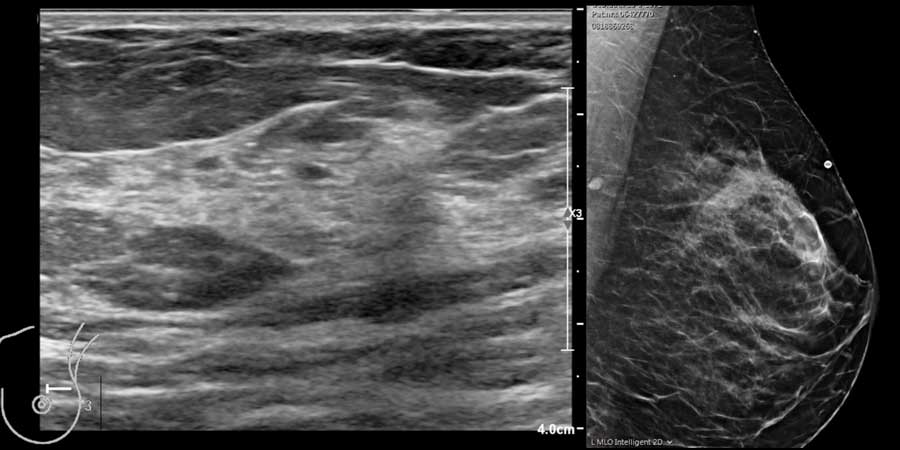

Thành phần mô vú

Siêu âm cho phép xác định thành phần mô vú: mô xơ tuyến đồng nhất – mô không đồng nhất – hoặc mô mỡ đồng nhất (hình).

Lưu ý rằng hình ảnh nhũ ảnh và siêu âm rất tương đồng nhau.

Ở phụ nữ trẻ, vú chủ yếu chứa mô tuyến.

Mô tuyến này có thể rất phát triển trong thời kỳ mang thai và cho con bú, đồng thời có thể biến đổi theo chu kỳ ở phụ nữ tiền mãn kinh, khiến vú có cảm giác u cục hoặc đau.

Ở phụ nữ lớn tuổi, mô tuyến dần được thay thế bởi mô mỡ, mặc dù một số phụ nữ lớn tuổi vẫn có thể còn một lượng mô tuyến đáng kể.

Ở phụ nữ béo phì, lượng mỡ trong vú nhiều hơn ngay cả ở độ tuổi trẻ hơn.

Trong cùng một tuyến vú có thể tồn tại các vùng có nhiều mô mỡ xen kẽ với các vùng chủ yếu là mô xơ tuyến, như có thể thấy trên video.

Khi quan sát đường bờ của mô tuyến (mũi tên), có thể hình dung rằng khi sờ nắn sẽ cảm thấy gồ ghề và đôi khi tạo cảm giác như có một khối u khi mô tuyến rất phát triển.

Hình ảnh vú trên siêu âm có thể khác nhau tùy theo máy của các nhà sản xuất khác nhau.

Điều này có nghĩa là cần làm quen với hình ảnh trên máy siêu âm của chính mình.